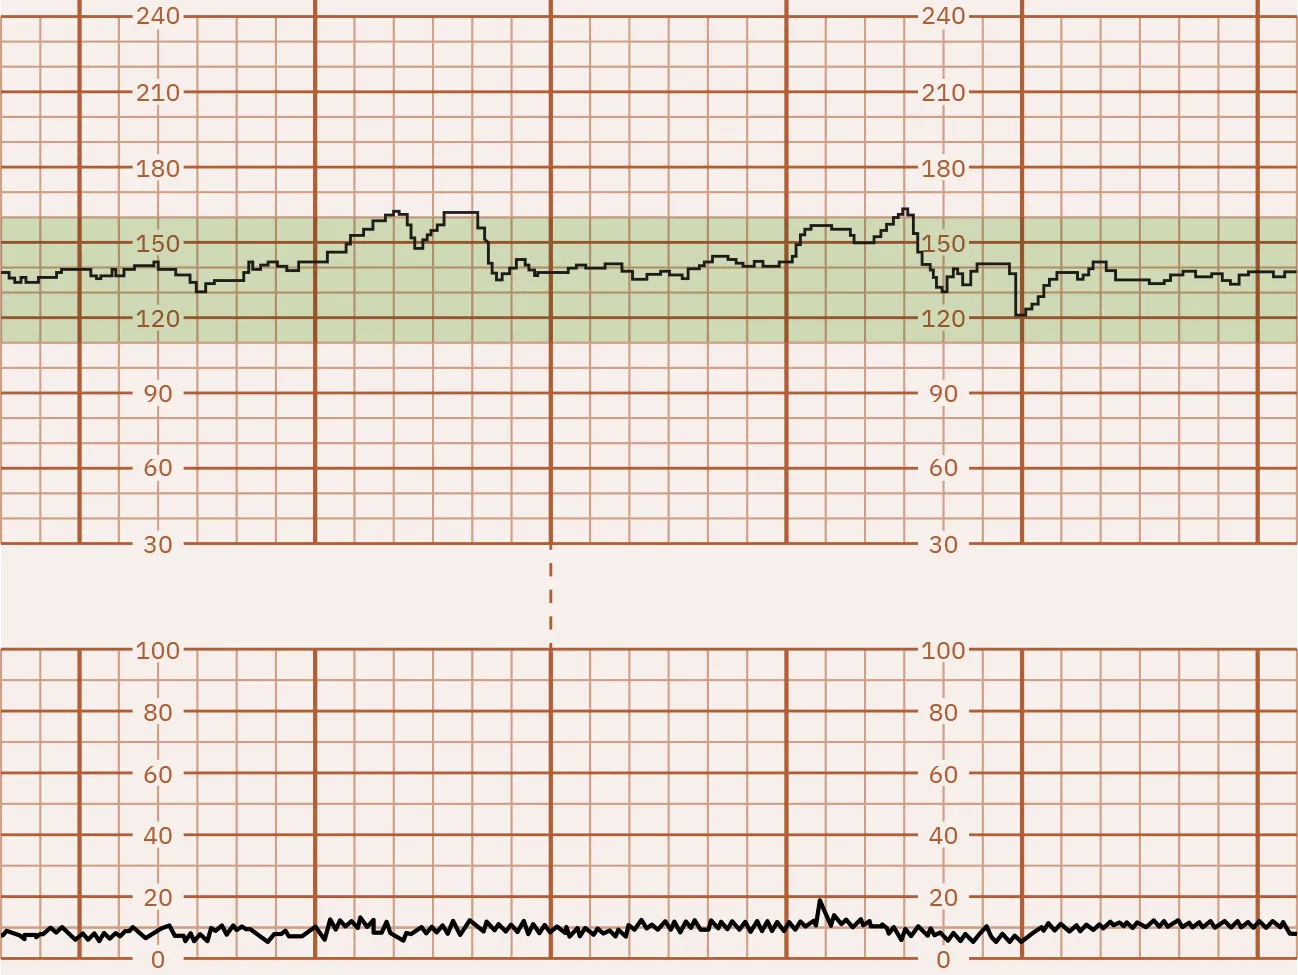

Uterine contractions are monitored for frequency, intensity, and duration. As discussed in Chapter 15 Process of Labor and Birth, the frequency is how many minutes from the start of one contraction to the start of the next contraction. Intensity is the strength of the contraction. Duration is the number of seconds from the start to the end of a contraction.

As shown in Figure 16.15, the monitor graph is divided by darker or more prominent vertical lines to represent 1 minute of time and less prominent vertical lines showing 10-second intervals. The upper set of horizontal lines represents the fetal heart rate in beats per minute (bpm), usually in intervals of 10 bpm. The lower set of horizontal lines represents the intensity of the contractions in millimeters (mm) of mercury (Hg), in intervals of 5 to 10 mm Hg.

An image showing a fetal heart rate and uterine contraction monitoring graph. The top graph represents the fetal heart rate with a line oscillating around 120 beats per minute, marked by regular vertical red lines. The bottom graph shows uterine contractions with three bell-shaped curves aligning with the red lines above, and green lines indicating the start and end of contractions.

Figure 16.15 Fetal Heart Rate and Contraction Monitor Graph This monitor tracing shows the fetal heart rate baseline of 130. The contraction frequency is 2 to 3 minutes. The contraction duration is 45 to 70 seconds. The contraction intensity is 50 to 70 mm Hg. (attribution: Copyright Rice University, OpenStax, under CC BY 4.0 license)